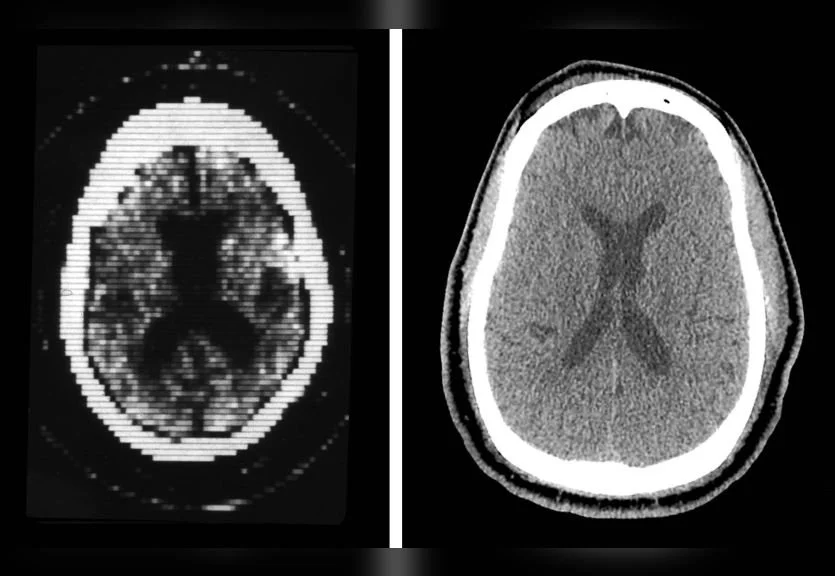

Side-by-side comparison of early CT imaging and modern scan quality.Image courtesy of Yale School of Medicine

Side-by-side comparison of early CT imaging and modern scan quality. Image courtesy of Yale School of Medicine